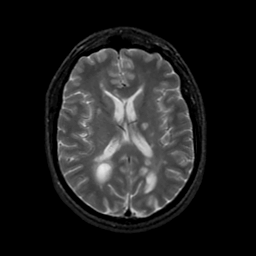

MR Study #22, December 1, 1991 -- Slice #29